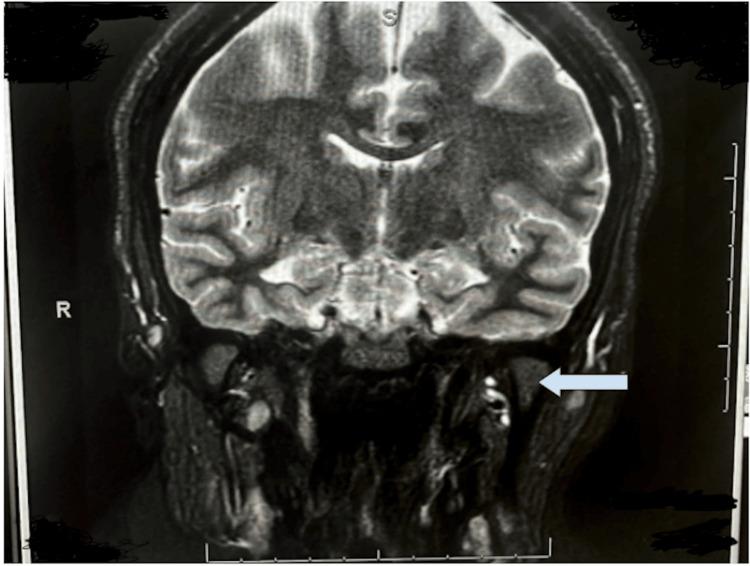

Idiopathic intracranial hypertension (IIH) is a clinical diagnosis made from the exclusion of other possible causes of increased intracranial pressure (ICP): cerebrospinal fluid (CSF) overflow obstruction, mass lesion, infection, or malignancies. IIH is a phenomenon with a rapid onset that most notably presents in obese women of childbearing age. We present the case of a 30-year-old African American woman with a past medical history of bipolar disorder who arrived at the emergency department (ED) with acute bilateral vision loss, two weeks of bilateral retro-orbital headache, painful eye movements, and progressive vision loss with a decrease in appetite. Management involved plasma exchange, high-dose steroids, consistent neurological and ophthalmic tests, and close observation and follow-up. One week after the most recent ED visit, the patient confirmed a significant improvement in vision. When diagnosing our patient with IIH, it was imperative to rule out myelinating oligodendrocyte glycoprotein antibody-associated disease (MOGAD), multiple sclerosis (MS), and other demyelinating diseases such as optic neuritis. Initial brain imaging using computed tomography (CT) without contrast showed no evidence of intracranial hemorrhage but demonstrated the presence of prominent sheath complexes, suggestive of optic neuritis, and a slightly small pituitary gland height for a patient who is 30 years of age. Further testing with a CT venogram (CTV) and a magnetic resonance imaging (MRI) of the head and neck confirmed demyelination. The patient's lumbar puncture continuously revealed a normal opening pressure during her hospital stay. This case presentation will highlight and compare the current literature regarding the clinical presentation and management of idiopathic intracranial hypertension.

特发性颅内高压(IIH)是一种通过排除颅内压(ICP)升高的其他可能原因而做出的临床诊断:脑脊液(CSF)溢流阻塞、占位性病变、感染或恶性肿瘤。IIH是一种起病迅速的现象,最常见于育龄肥胖女性。我们报告一例30岁非裔美国女性病例,她有双相情感障碍病史,因急性双侧视力丧失、双侧眶后头痛两周、眼球运动疼痛、视力进行性下降伴食欲减退而到急诊科就诊。治疗包括血浆置换、大剂量类固醇、持续的神经和眼科检查以及密切观察和随访。在最近一次急诊科就诊一周后,患者确认视力有显著改善。在诊断我们的患者患有IIH时,必须排除髓鞘少突胶质细胞糖蛋白抗体相关疾病(MOGAD)、多发性硬化症(MS)和其他脱髓鞘疾病,如视神经炎。最初使用无对比剂的计算机断层扫描(CT)进行脑部成像,未发现颅内出血迹象,但显示存在明显的鞘复合体,提示视神经炎,且对于一名30岁的患者来说,垂体高度略小。进一步通过CT静脉造影(CTV)以及头部和颈部的磁共振成像(MRI)检查确认了脱髓鞘。患者住院期间腰椎穿刺持续显示初压正常。本病例报告将突出并比较当前关于特发性颅内高压临床表现和治疗的文献。